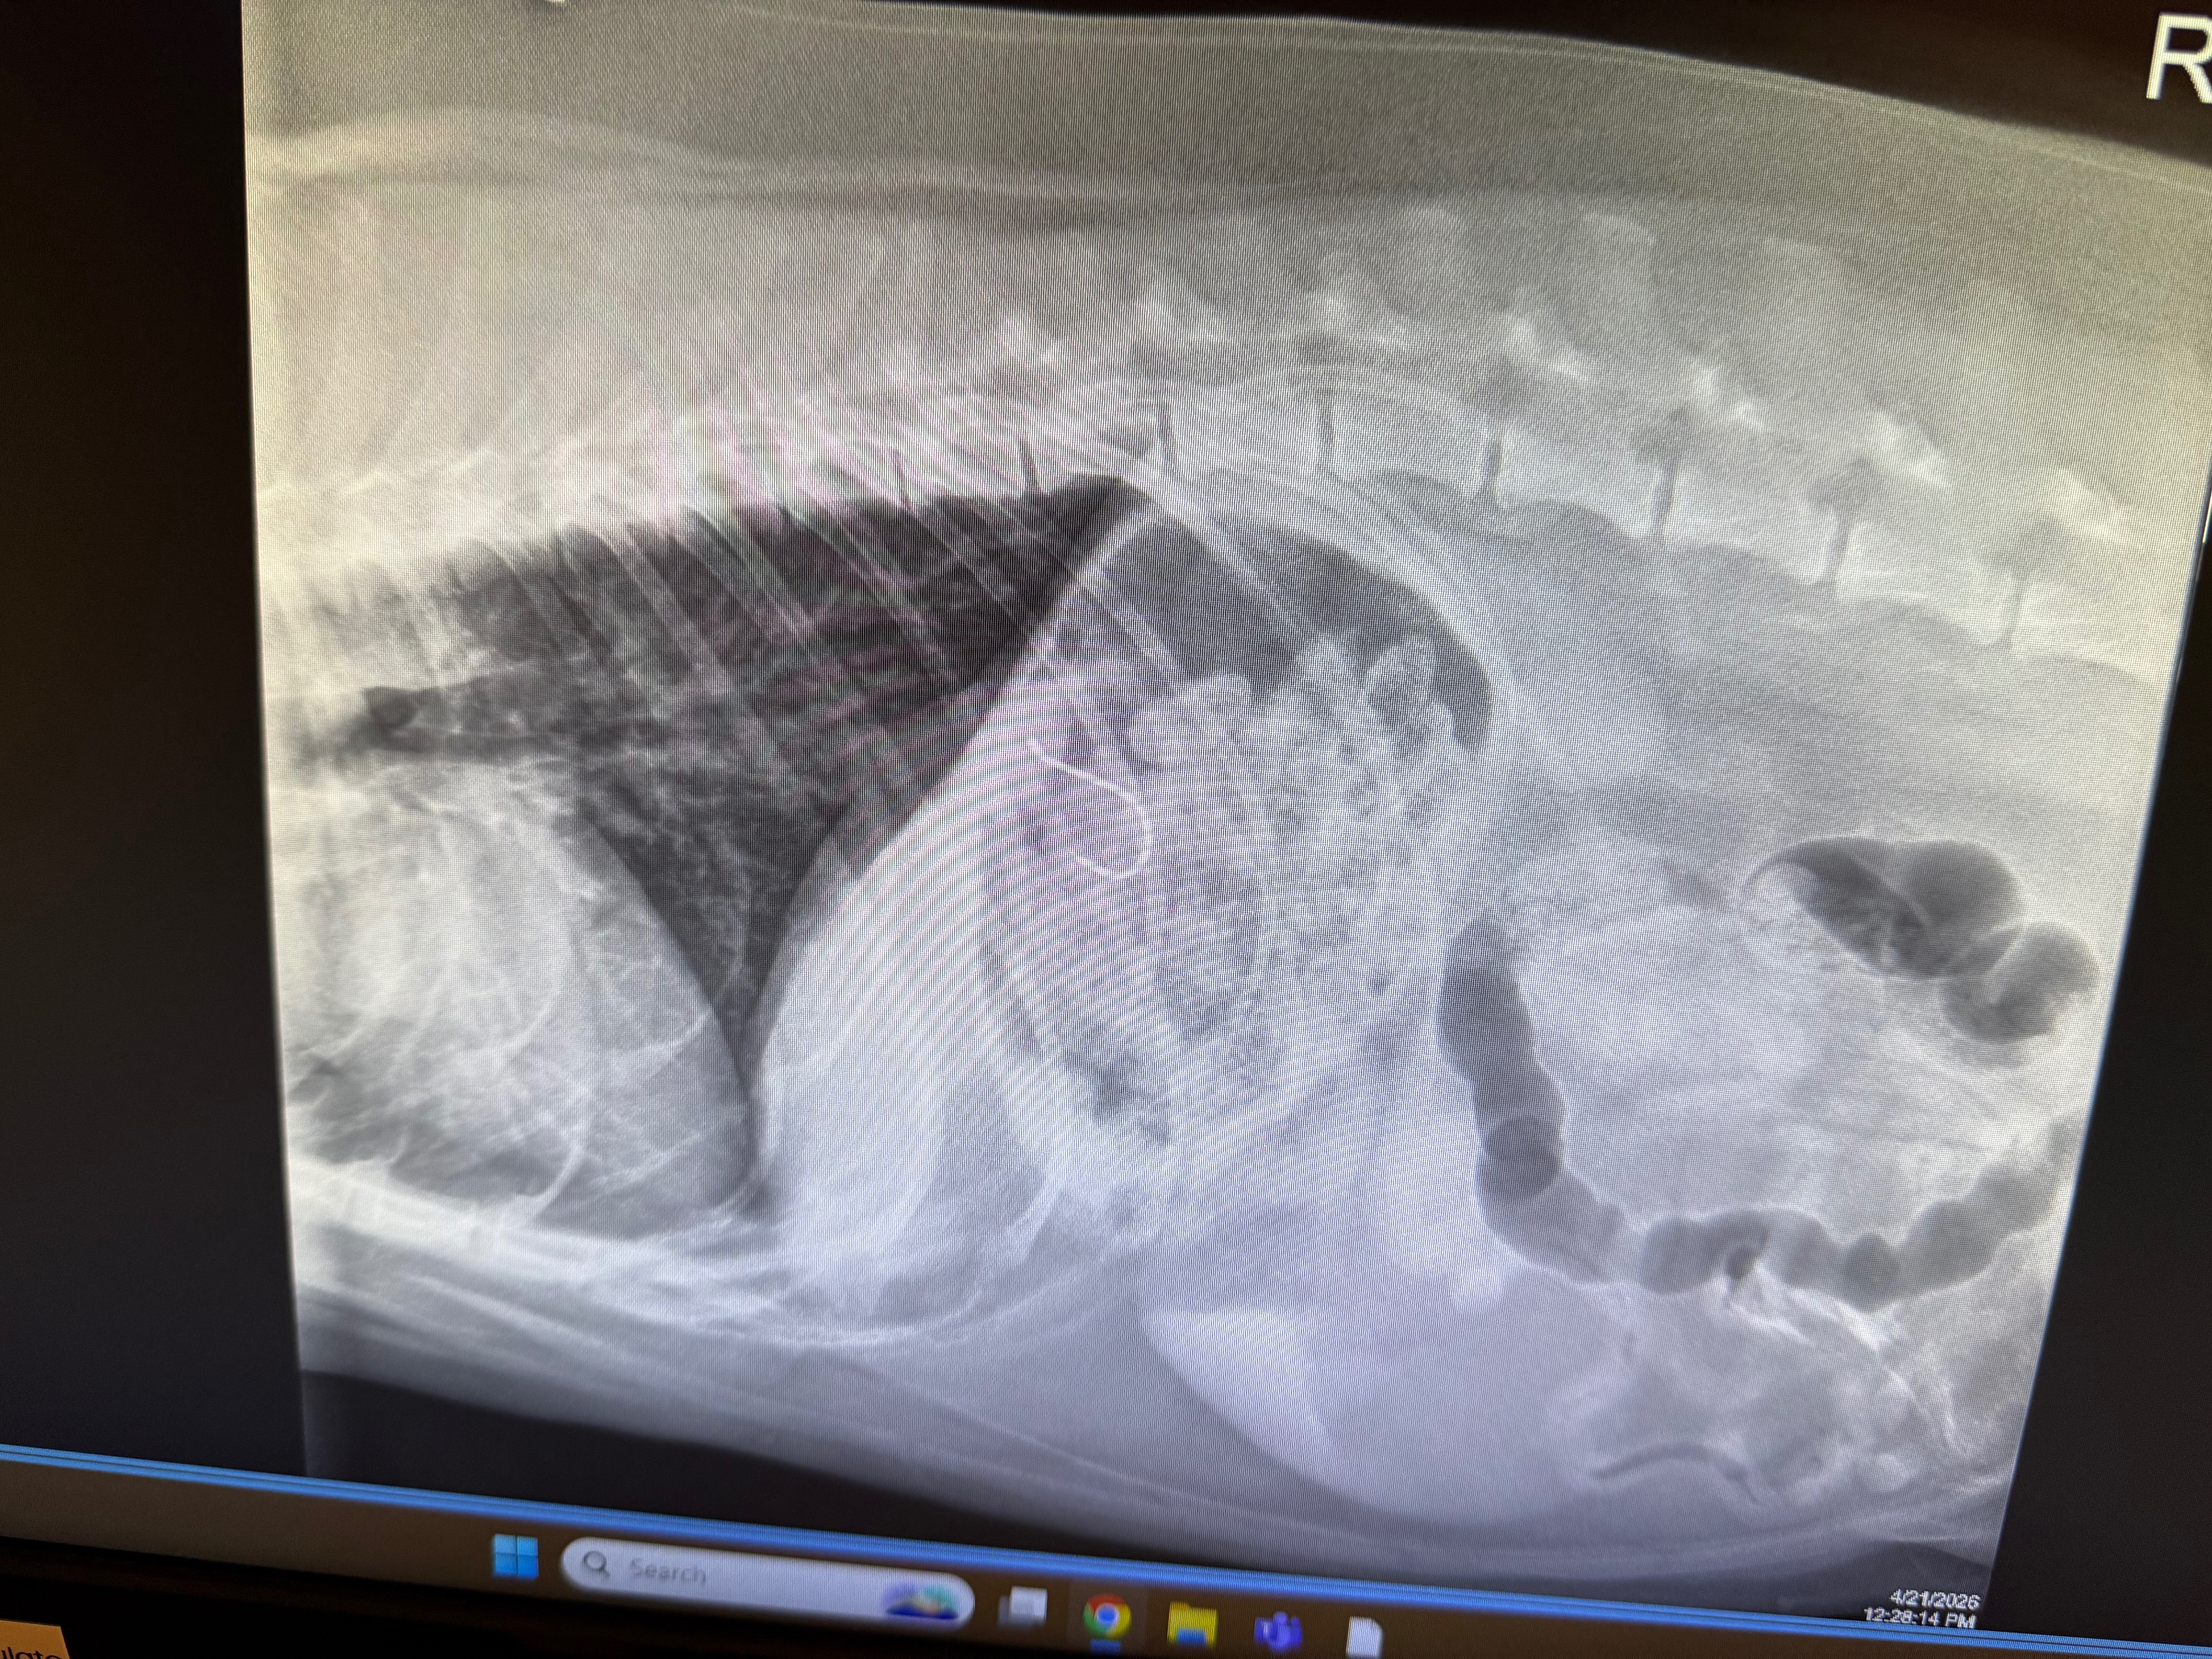

As much as we hate to ask for this, we need some serious help with our Siberian husky. We were walking her in Dana Point Harbor and someone left a fishing line with bait on it. Being the girl she is, she went for it and swallowed the fish hook. We immediately took her to emergency vet services, where they said she had already fully swallowed the hook and it was in her stomach. The fishing line was still hanging out of her mouth with the lure attached, so the line ran all the way to her stomach! They performed surgery to remove it and fortunately saved her from any puncture wounds, but not without leaving us with a near $6,000 bill. Anything, anything, anything helps. We would never put our girl in a place where she couldn’t be cared for, and are asking anyone to help who can. She is such a loved girl and is getting old. We’re hoping this is the last of any more medical bills, assuming she has no infections later on.